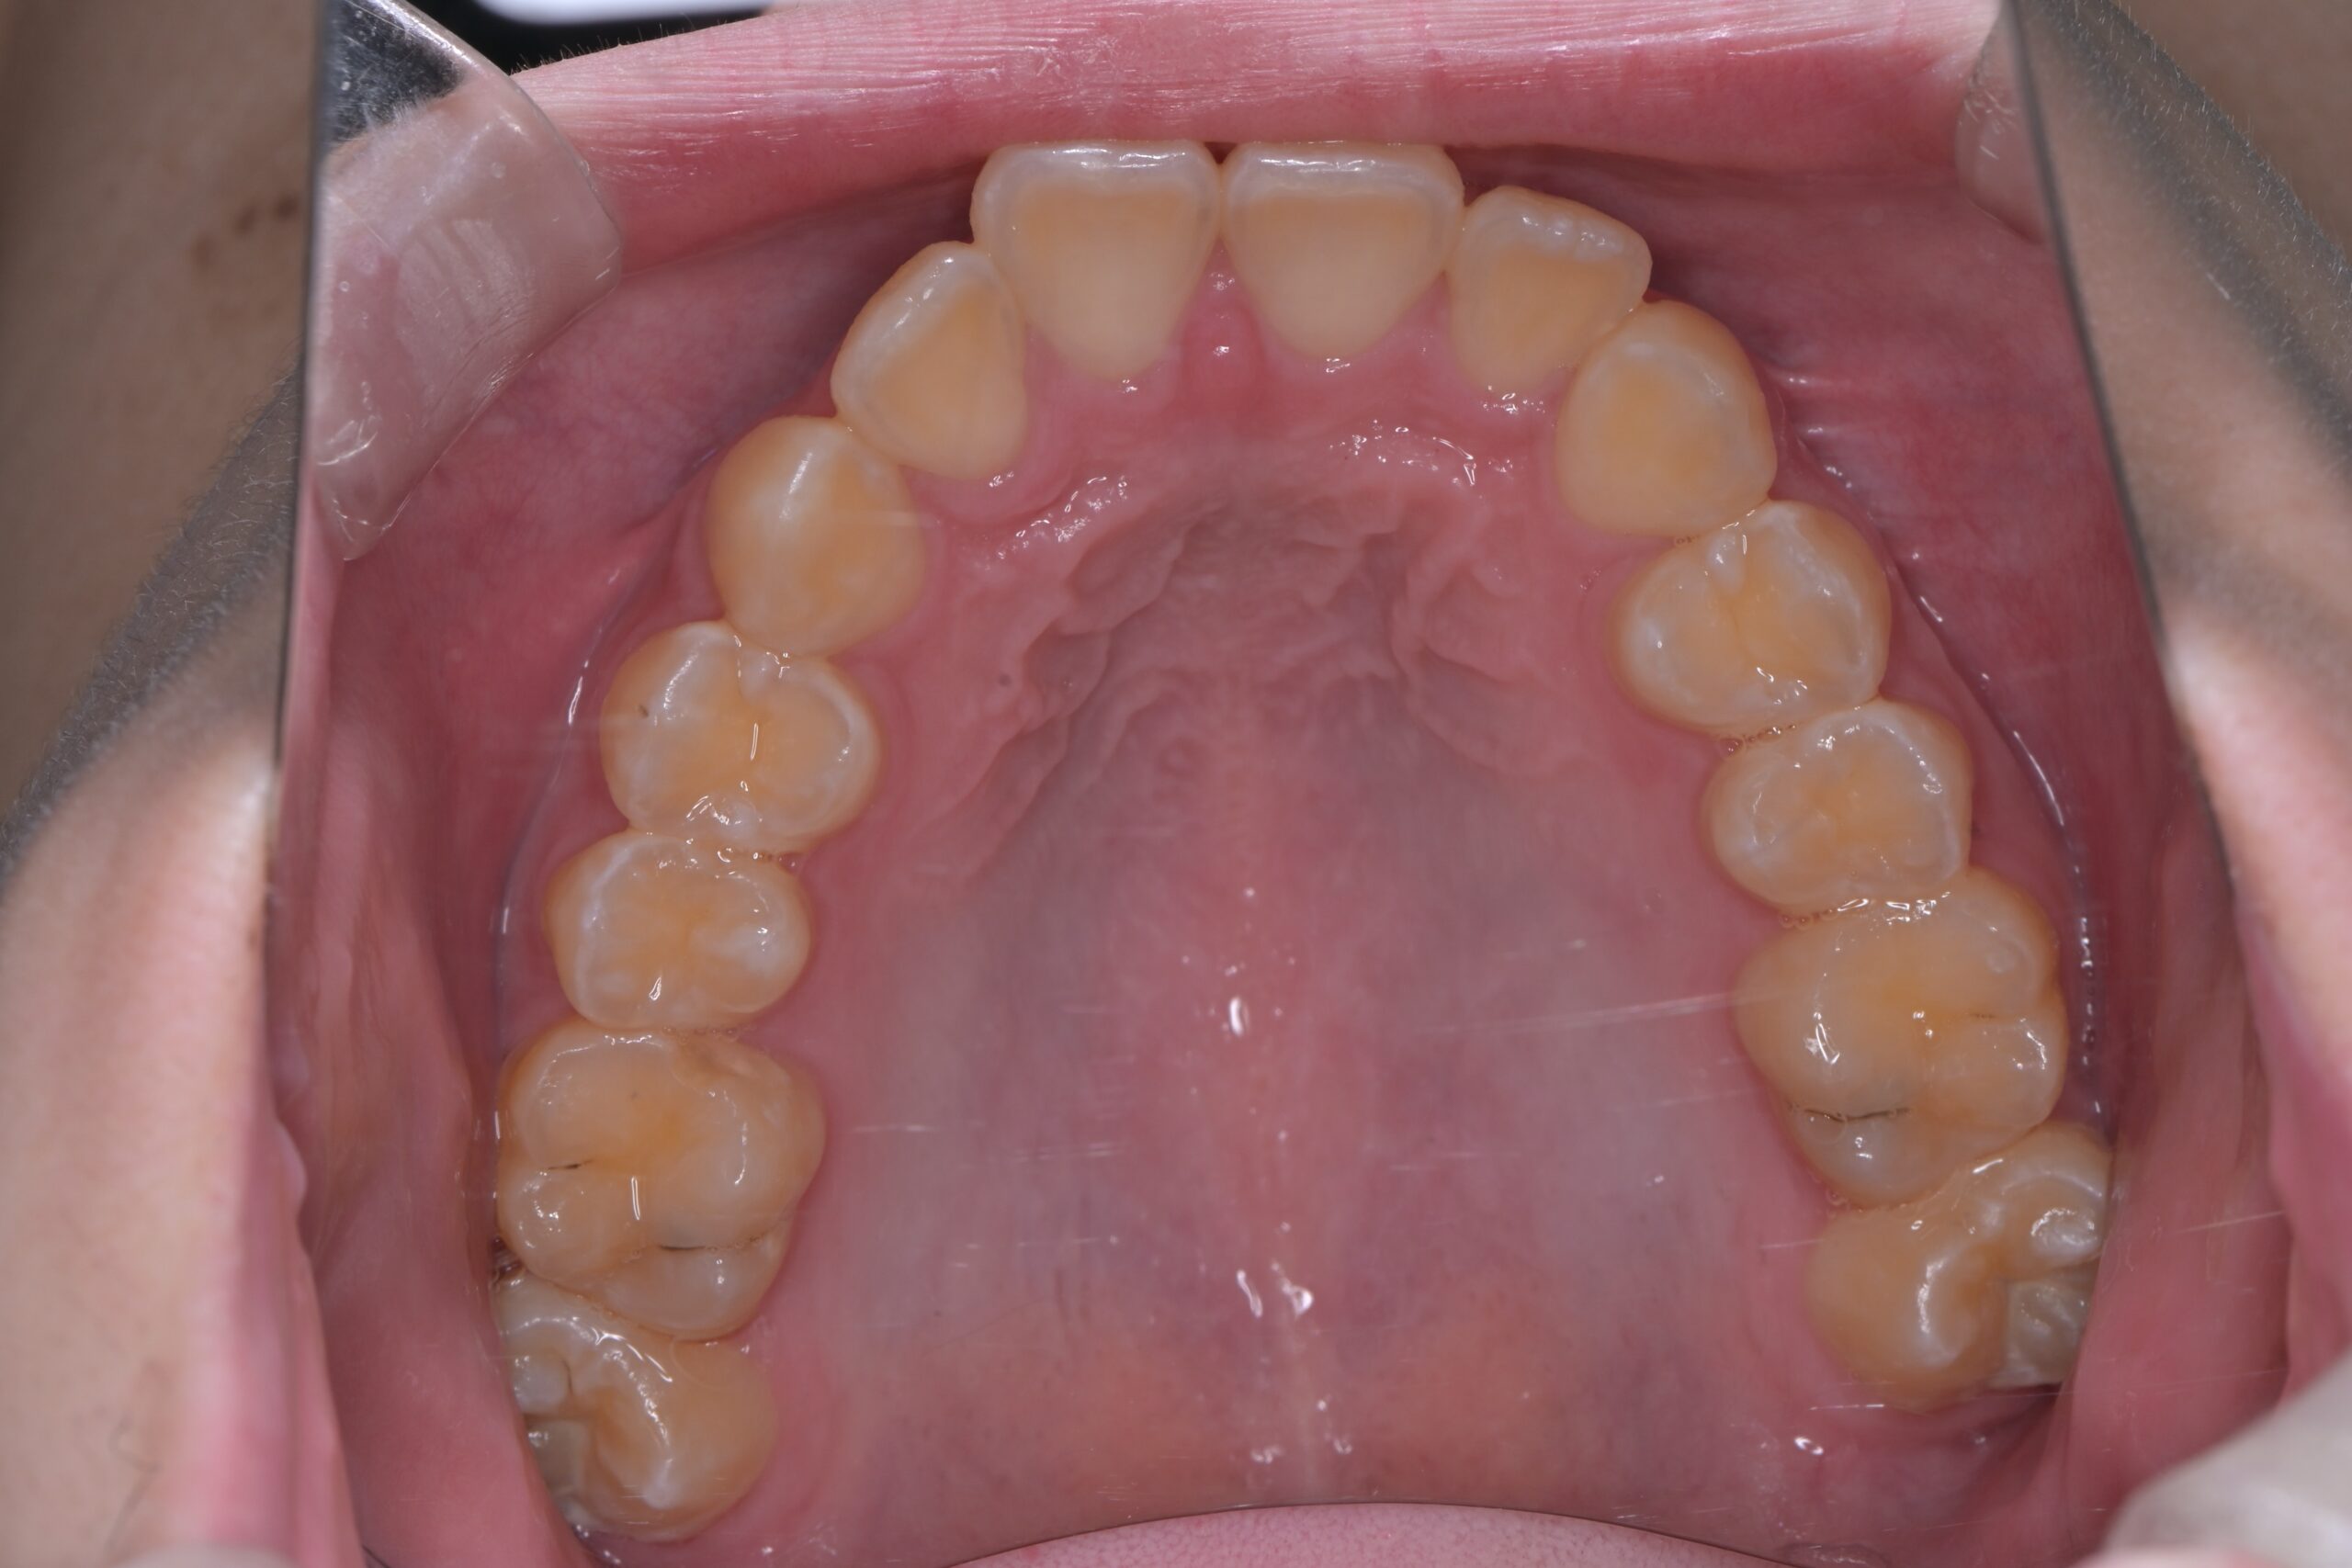

装置除去(上顎)